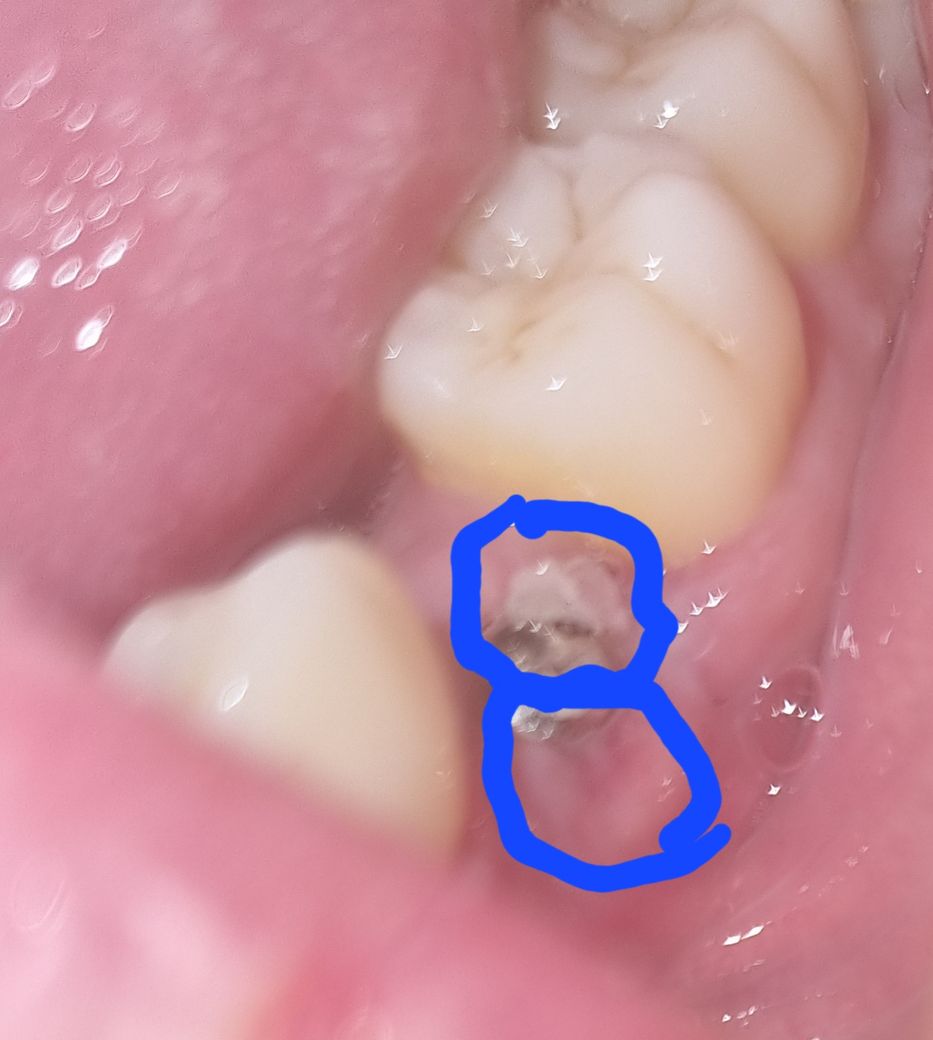

실밥 제거했고 오늘 좀 임플란트 부위가 간질거려서 확인했는데 잇몸에 하얀 부분과 아래 빨간 부분이 있어서 염증인지 걱정됩니다.

쇠구슬 처럼 보이는 것은 임플란트 덮게 나사이며 하얀 것은 딱지 앉은 것이며 빨간 부위는 아직 부위가 덜 빠지고 완전히 아물지 않은 것이니 그냥 두면 될 것으로 보입니다.

임플란트 나사와 육아조직 및 상피조직이 보이는 것 같으며 정상적인 치유과정으로 보입니다. 걱정하지 않으셔도 됩니다

하얀 부분은 잇몸이 치유되는 조직, 빨간 부분은 치유중으로 보여집니다.